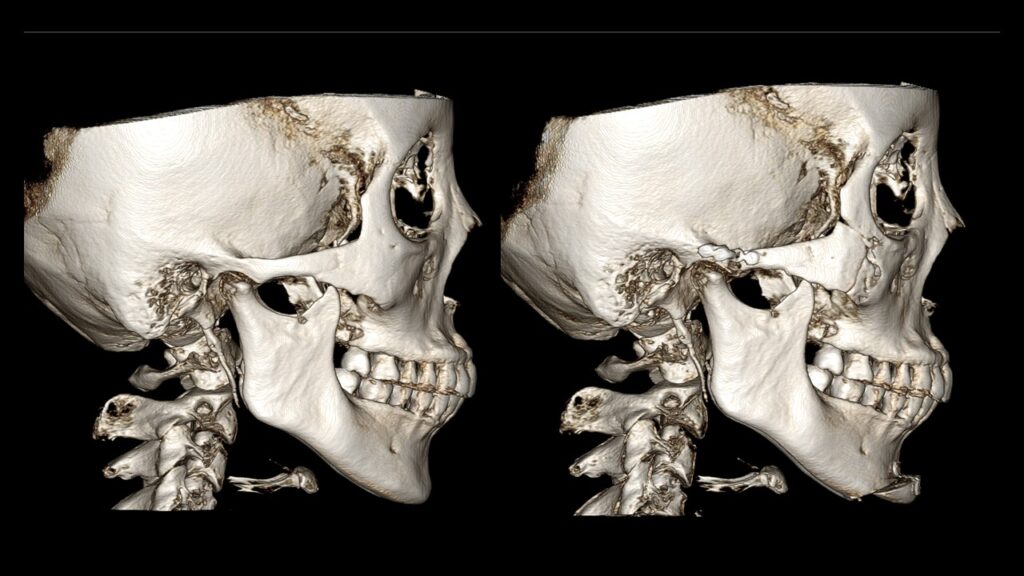

4. Case Studies (3DCT & Medical Photos)

Case 1: (Zygoma Reduction + Face Lift) 1-year post-op shows a significant reduction in mid-face width and improvement in nasolabial folds.